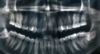

during 3rd molar assessment what does an OPT determine?

Presence or absence of disease (in 3M or elsewhere)

Anatomy of 3M (crown size, shape, condition, root formation)

Depth of impaction

Orientation of impaction

Working distance (distal of lower 7 to ramus of mandible)

Follicular width

Periodontal status

The relationship or proximity of upper third molars to the maxillary antrum and of lower third molars to the inferior dental canal

Any other assoc pathology